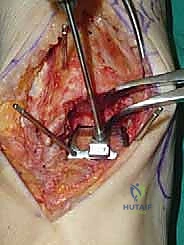

يقوم الدكتور هطيف بعمل شق طولي دقيق في الجزء الأمامي من الكاحل، طوله حوالي 10-15 سم. يتم تشريح الأنسجة بعناية فائقة للوصول إلى المفصل.

* الحماية العصبية الوعائية: هذه هي الخطوة الأكثر حرجاً. يتم تحديد الحزمة الوعائية العصبية (الشريان الظنبوبي الأمامي والعصب الشظوي العميق) وسحبها برفق شديد لحمايتها من أي ضرر جراحي.

3. إزالة النتوءات العظمية وتحضير المفصل (Debridement)

بمجرد كشف المفصل، يقوم الجراح بإزالة الغشاء الزلالي الملتهب والزوائد العظمية (Osteophytes) التي تعيق الحركة. هذه الخطوة ضرورية لاستعادة المعالم التشريحية الطبيعية قبل إجراء القطع العظمي.